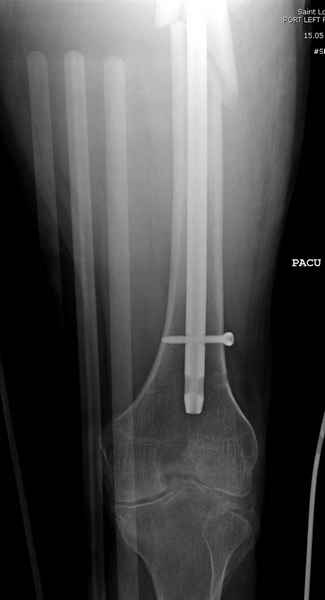

Учитывая, что случай ургентный, больной поступил вечером, не стали делать вытяжение и срочно провели операцию по фиксации перелома бедра антеградным штифтом Versa Nail от DePuy.

Для профилактики дальнейшего раскола в шейке предварительно во время проксимального рассверливания спереди и сзади провели временные спицы, которые в дальнейшем были заменены на шурупы (miss nail method)

Обычная спасательная фасциотомия для обычного больного в этом случае было бы приговором, поэтому несмотря на высокие цифры компартментального мониторинга больного оставили под наблюдением с обкладкой конечности льдом.

Кровотечение удалось контролировать, и больной через пару дней выписан на амбулаторное лечение.